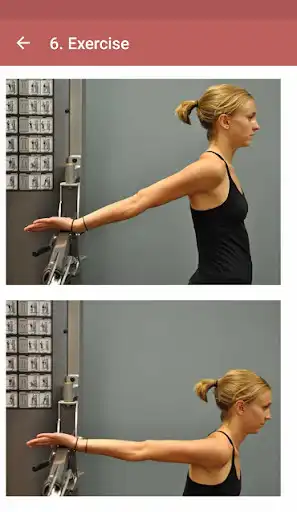

Rotator cuff tears can be caused by sudden and backward movement of the shoulder, excessive strain of the shoulder, and falling. Symptoms are usually shoulder pain, a clicking sound from the shoulder while moving the arm, and limitation of movement and muscle weakness.

After the examination, the patient is directed to surgical or other shoulder treatment methods according to the degree of the tear. Exercise therapy is recommended for less severe tears.

In our mobile application, exercises to help treat rotator cuff rupture are shown. When you repeat these movements regularly, shoulder pain decreases, range of motion increases and shoulder muscles become stronger.